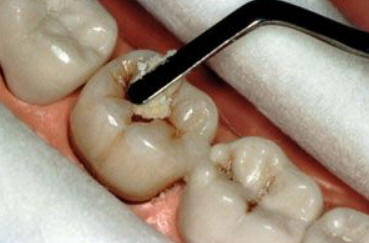

Imagen digital que representa la microfiltración y penetración del sellante realizado.

Microfotografía: Muestra como el sellador obtura la caries subyascente, evitando su avance.

Código 3 (Caries moderada) in vitro. Los códigos 3 in vivo debe ser sellado para evitar el avance del proceso carioso. (MNO)

Código 4 (Caries moderada) in vitro. Los códigos 4 in vivo deben ser tratados en forma operatoria con preservación dental (MOPD), porque presentan dentina infectada.